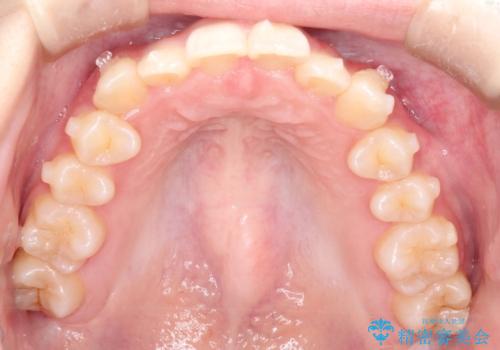

- 前歯のガタガタを主訴に来院された患者様です。

八重歯になっており、下顎の前歯が上顎の前歯に隠れてしまう、ディープバイトという状態でした。

インビザラインを使用して矯正する計画としました。

ディープバイトの場合、ワイヤー装置の装着が難しいことがあります。

インビザラインではかみ合わせに左右されず装着できるメリットがあり、ワイヤーに比べインビザラインの方が治療しやすい場合もあります。